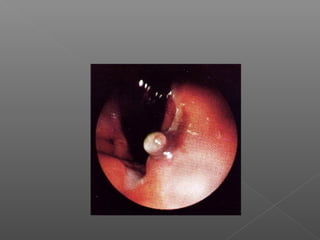

III. Métodos mecánicos

Hemoclips

Bandas elásticas

Endoloops

Hemocl

ips

Colocación de Hemoclips